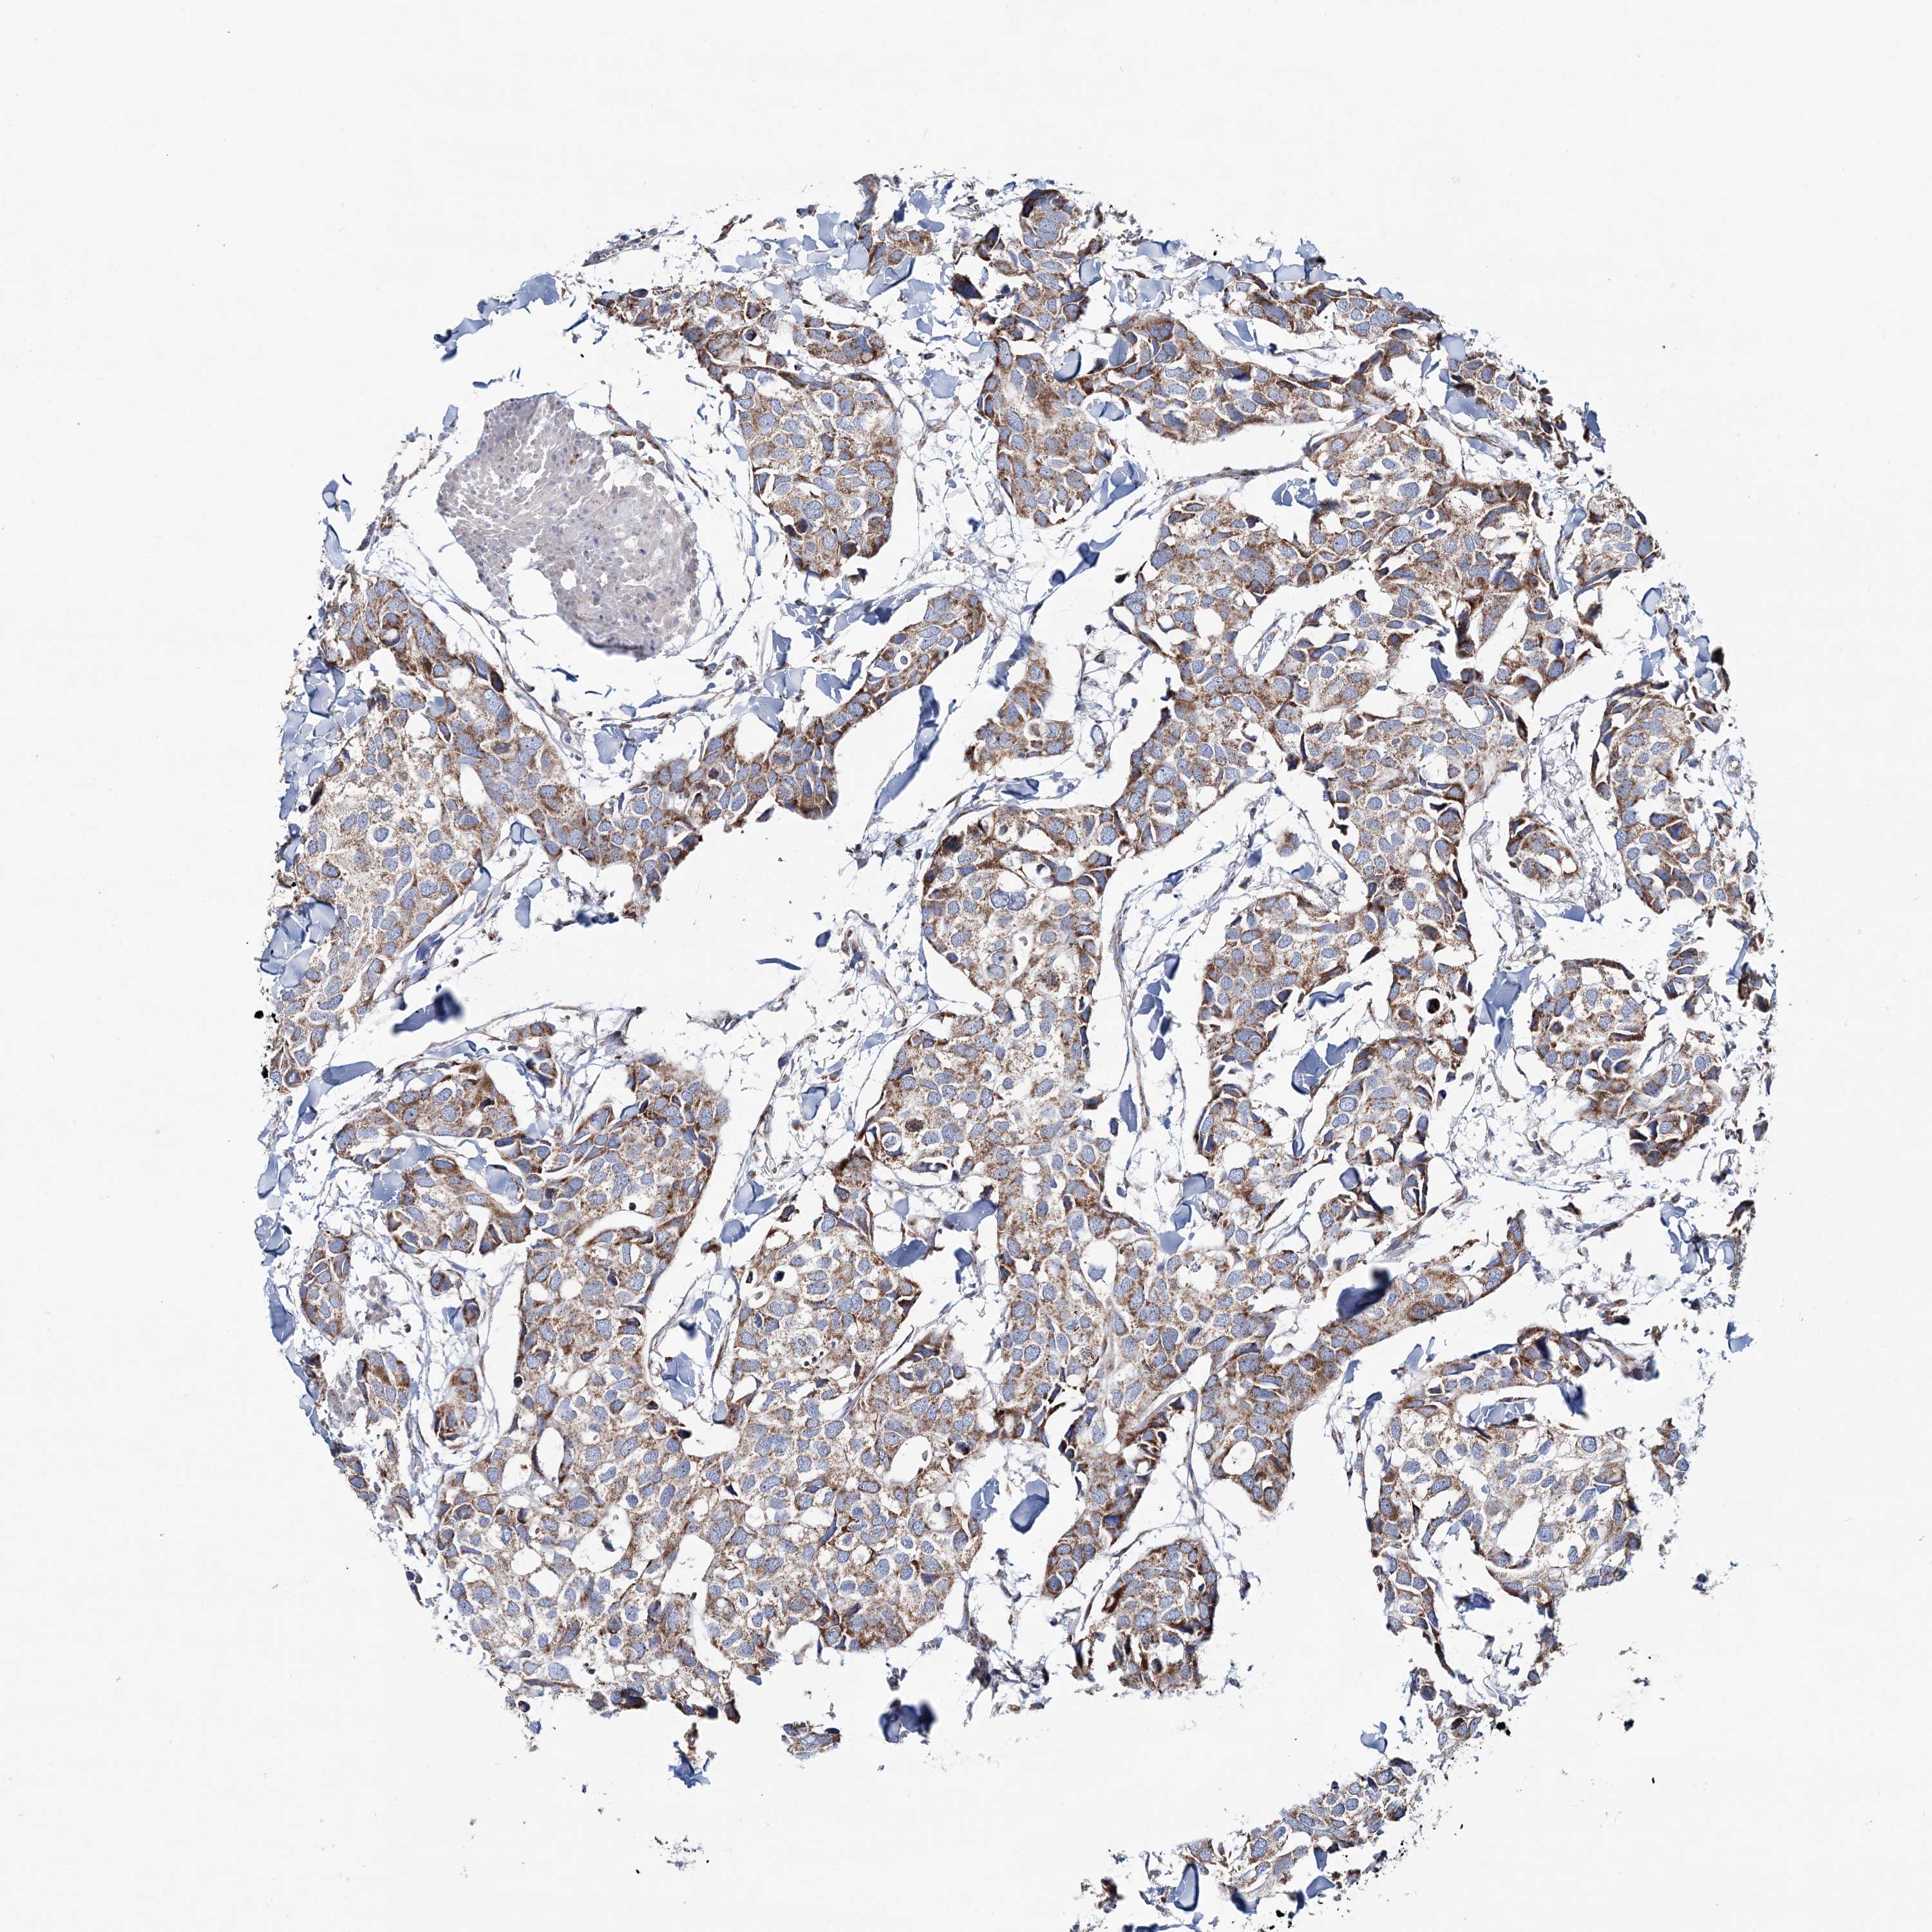

CANCER BREAST CANCER Show tissue menu

BRCA TCGA BRCA VALIDATION PROTEIN EXPRESSION

ANTIBODIES

AND

VALIDATION